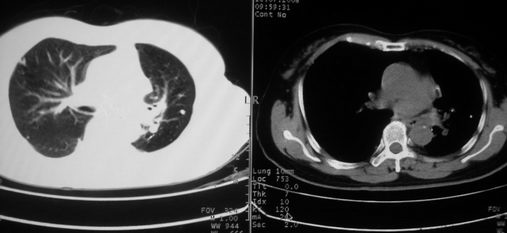

以下是引用李衡钧在2008-7-24 14:24:00的发言:[br]左侧胸廓变小,左肺上叶见大面积致密阴影,其内有空洞及不规则钙化。上纵隔略向左移位,上肺胸膜增厚。左肺门及纵隔淋巴结增大。右肺见散在的致密结节影。[br]印象:继发性肺结核。